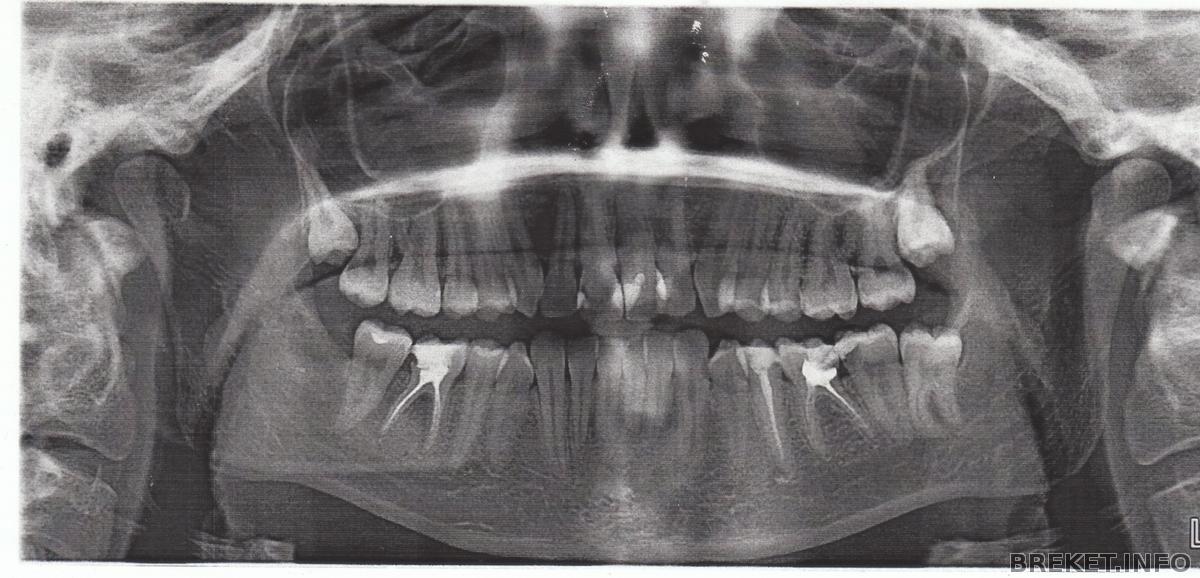

Вот она четвёртая неделя уже подходит к концу моего ношения железочек! Впечатления отличные. Только еда застряёт. Совсем никаких проблем! Чистятся легко. Ничего не трёт (перестало на второй день. быстро адаптировалась). Тройка уже тронулась окупировать свободное место от четвёрки) начну с маленькой предистории. Решилась на установку БС спустя 6 лет после первого ортодонтического лечения (пластинка на ВЧ и только. Помогла, но не очень, ибо скупченность порядочная, а места маловато, но в тот момент я не решилась на удаление и ношение еще одного года как минимум, железок и уже несъемных). А тут многие факторы подтянули меня к тому, что мне это необходимо! А началось всё с мысли : "Мне нужен Голливуд любым способом"... вернее в способах-то я вот как раз и ограничилась, думая, что протезист исправит без ортодонта, но я ошибалась. Из-за поворота передних зубов моя зубная фея развела руками, мол: Иди к ортодонту или смирись с этим! Выслушала я от неё три лекции по поводу моих безумных идей в стиле : "Выровнять ряд за счет протезирования без ортодонтического лечения". Короче, больше распиналась. Уже б давно ходила с ровненькими зубками, если бы столько не очковала. НО! Всё-таки доочковалась до верного решения, ибо этот год оказался весьма продуктивным (даже не знаю в хорошем или плохом смысле) для принятия этого решения. Лекции моей феи по поводу невозможности Голливуда без ортодонтии, здравого смысла , восьмерка на НЧ, разболевшая всю челюсть своим эффектным выходом (которую в итоге пришлось удалить из-за близкого положения к семерке. Была ретенированной и давила на корни так, что болело всё: голова, обе челюсти, глаза, уши. Стреляло так, что думала: ну всё! Первая мировая зубная началась) и под конец еще воспаленная десна с абсцессом между депульпированным шестым зубом и седьмым на той же стороне. К тому же за полгода до этого моя фея порадовала меня, что четверки на ВЧ поражены кариесом и опоясаны тёмными пятнами и спасти их уже нельзя. Мол, пока не болят - ходи, а потом удалишь. если че. Вобщем, представив себя без двух четверок со скупченностью во фронтальных зубах при этом, я пришла в ужас. Но опасаясь за восьмёрки , я не спешила к ортодонту. Ибо одну восьмерку удалила по вынужденным обстоятельствам, а вот вторую полуретинированную терять не хотелась. Сделала панораму и узрела, что на верхней тоже пошли восьмерки вширь на выход и боязнь моя стала еще сильнее.